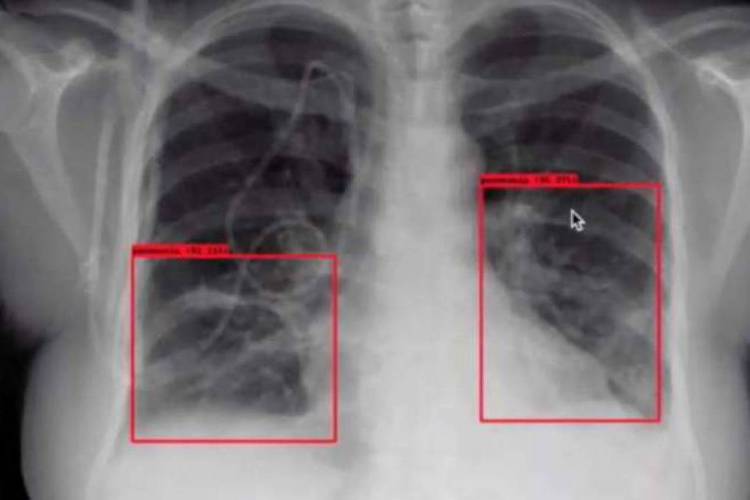

Essa não é a única ferramenta que a PickCells desenvolveu em tempo recorde para ser usada diante da pandemia. Outra solução ajuda no diagnóstico da pneumonia típica da covid-19, que tem características trombóticas. A inteligência artificial analisa imagens de raios-X (foto) ou tomografias computadorizadas e busca padrões que indiquem que o paciente está com os pulmões comprometidos – e essa é a principal causa de agravamento do doença.

“Essa análise não substitui o trabalho do radiologista, mas o ajuda a localizar rapidamente padrões que indicam a forma grave da doença, que nem sempre manifesta sintomas nos primeiros dias”, diz Melo.

Assim como no exame bioquímico, a startup está na fase de treinar a IA para fazer a análise das imagens. A empresa vai receber cerca de 300 exames de um hospital de São Paulo para que o estudo dessas imagens “ensine” a IA a ser ser cada vez mais eficiente na detecção da pneumonia. “Buscamos um índice de assertividade na casa dos 85%. Mas acreditamos ser possível chegar a 94%”, acrescenta Paulo Melo.